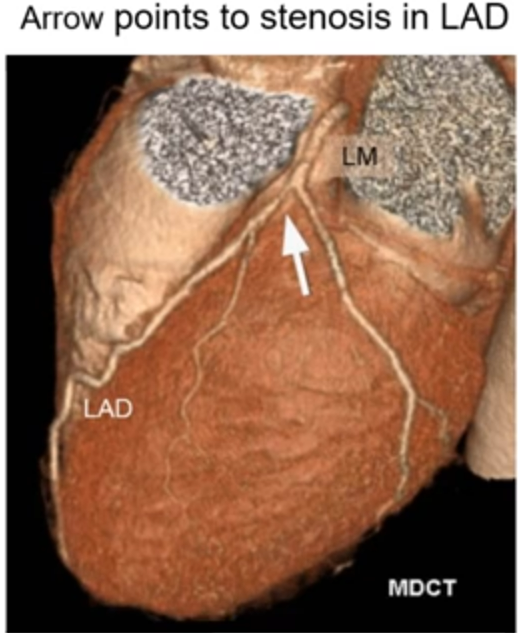

• CT coronary Angiogram

• requires the administration of IV contrast to visualise non-calcified plaque and estimate the severity of luminal stenoses

• allows for high resolution assessment of the presence, extent and severity of, coronary plaque

• currently, the greatest potential clinical value of coronary CTA is in the evaluation of low - intermediate patients with symptoms of possible coronary ischaemia